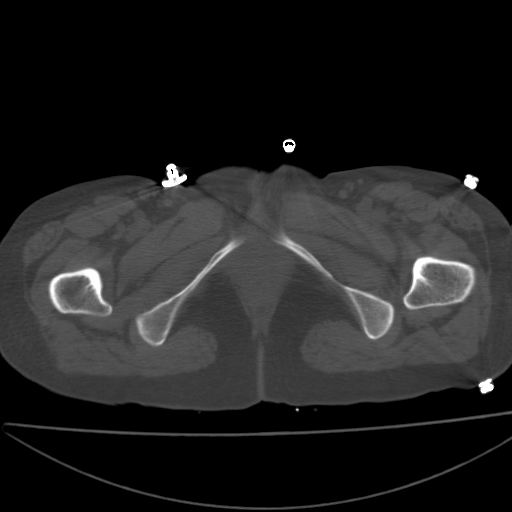

以下是引用xiaoniu在2008-9-6 8:22:00的发言:[br]右侧股骨颈囊性低密度,囊壁边缘硬化,中年妇女,首先考虑:骨囊肿。其次考虑动脉瘤样骨囊肿。[br][br][br][本贴已被 xiaoniu 于 2008-9-6 9:04:54 修改过]